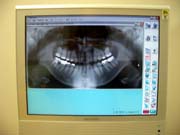

<デジタルレントゲン>

最新のデジタルレントゲンを採用してます。

従来のフィルム撮影に比べ、被曝量が大幅に軽減されていることが特徴です。

また、デジタル処理で行うため、撮影後すぐにご覧になれ、治療時間の短縮にもなります。

現像の際に廃液も出ないため、環境にも優しいものです。